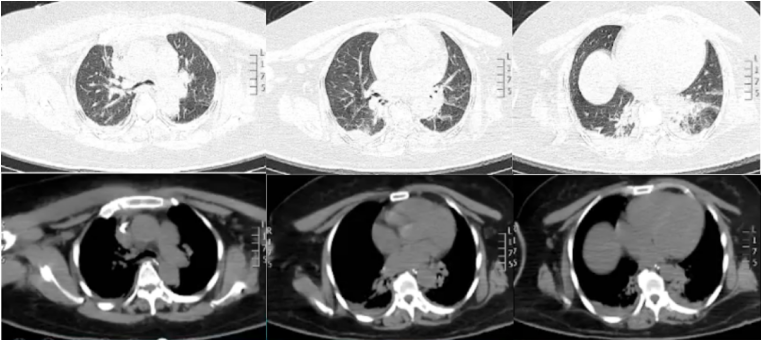

入院时查动脉血气(鼻导管吸氧2 L/min):pH 7.30,PaCO2 49 mmHg,PaO2 83 mmHg,HCO3- 24.1 mmol/L,SaO2 95%。血常规:WBC 13.13×109/L,Hb 123 g/L,NEU% 91.2%(↑)。PCT>100.0 ng/ml,CRP>200 mg/L。CREA 287.0 μmol/L,BUN 24.90 mmol/L。查骨盆X线示右股骨上段骨折内固定术后改变,双侧股骨头缺血坏死并髋关节退变,合并右髋关节脱位。胸部CT(7月28日):双下肺渗出、实变,双侧胸膜下少许胸腔积液(图1)。图1 患者入院后胸部CT